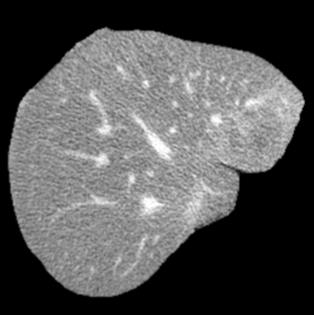

Manually segmenting the hepatic vessels from Computer Tomography (CT) is far more expertise-demanding and laborious than other structures due to the low-contrast and complex morphology of vessels, resulting in the extreme lack of high-quality labeled data. Without sufficient high-quality annotations, the usual data-driven learning-based approaches struggle with deficient training. On the other hand, directly introducing additional data with low-quality annotations may confuse the network, leading to undesirable performance degradation. To address this issue, we propose a novel mean-teacher-assisted confident learning framework to robustly exploit the noisy labeled data for the challenging hepatic vessel segmentation task. Specifically, with the adapted confident learning assisted by a third party, i.e., the weight-averaged teacher model, the noisy labels in the additional low-quality dataset can be transformed from "encumbrance" to "treasure" via progressive pixel-wise soft-correction, thus providing productive guidance. Extensive experiments using two public datasets demonstrate the superiority of the proposed framework as well as the effectiveness of each component.

翻译:将来自计算机地形学(CT)的肝脏船只人工分割,由于船只的低调和复杂形态,由于低调和复杂的形态,造成极端缺乏高质量的标签数据,因此比其他结构更需要专门知识和难度大得多。如果没有足够的高质量的说明,通常的数据驱动的基于学习的方法就会与不足的培训斗争。另一方面,直接引进低质量说明的额外数据可能会混淆网络,导致不良的性能退化。为了解决这一问题,我们提议建立一个新的、由教师协助的、有说服力的、有说服力的学习框架,为具有挑战性的肝脏船只分解任务强有力地利用响亮的标签数据。具体地说,在第三方(即加权平均教师模式)的协助下,经过变通的自信学习后,额外低质量数据集中的噪音标签可以从“阻力”转变为“压力”,通过渐进式的像素方法的软校正,从而提供富有成效的指导。使用两个公共数据集进行的广泛实验,显示了拟议框架的优越性以及每个组成部分的效能。